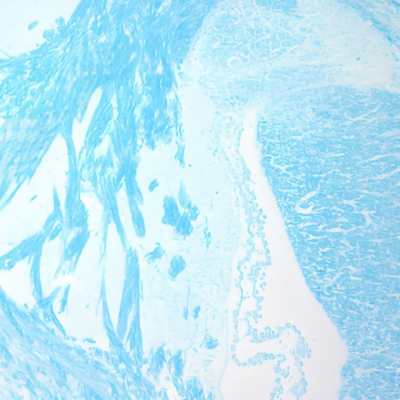

LFB染色(髓鞘)

¥25元/样

711